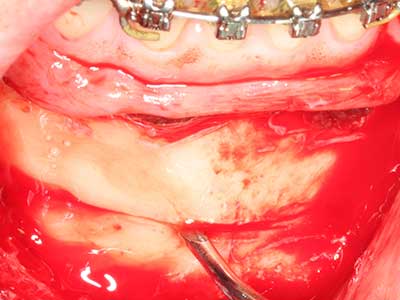

Sollen chirurgische Eingriffe mit unmittelbarer Knochenbeziehung an empfindlichen Strukturen wie Blutgefäßen oder Nerven erfolgen, so bergen rotierende Instrumente ein erhebliches Potential an iatrogener Schädigung. Gerade bei Nervdarstellungen nach iatrogener Schädigung, oder aber im Zuge einer Nervlateralisation für resektive und rekonstruktive Eingriffe oder Implantatinsertionen können piezoelektronische Geräte hilfreich sein Knochendeckel zu präparieren und nervnahe Hartgewebsanteile zu entfernen (Abb. 17-20). Ein leichter Kontakt des Nervstrangs zur Piezospitze bleibt dabei in der Regel folgenlos – allerdings kann eine unvorsichtige Vorgehensweise mit sägeartigen Bewegungen bzw. Ansätzen bei noch vorhandener knöcherner Unterlage durchaus temporäre oder aber auch permanente Nervschädigungen verursachen. Das Risiko einer solchen Schädigung wird jedoch als wesentliche geringer eingeschätzt als unter Anwendung von Säge- oder Fräsinstrumenten (Pereira, Gealh et al. 2014).